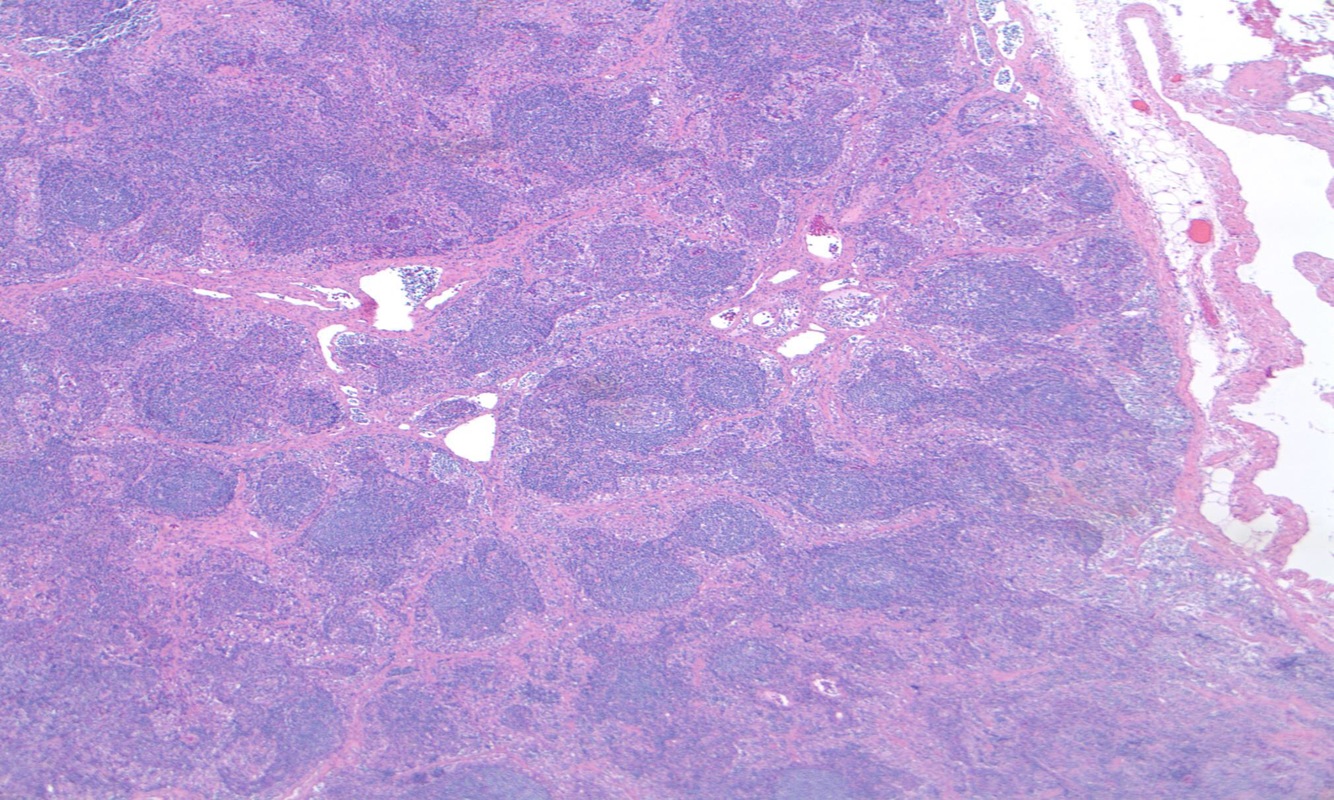

What does this image show?

Follicular hyperplasia

Paracortical hyperplasia